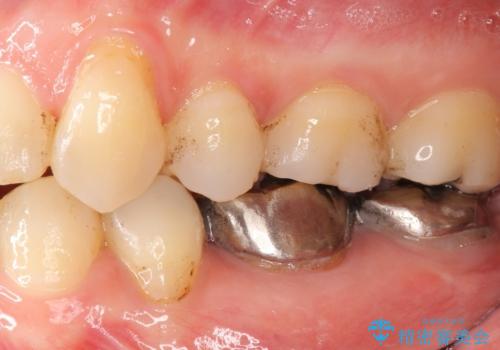

低予算で銀歯を白くしたい 50代女性

- 低予算で銀歯を白くしたいとご希望し来院された患者様です。

右上小臼歯(右上5)はオールセラミッククラウン(e-max press)、下顎臼歯(下顎両側67)はメタルボンドクラウンによりやりかえることにしました。

~クラウンの種類~

右上小臼歯(右上5):オールセラミッククラウン エコノミー

下顎両側臼歯(下顎両側67):メタルボンドクラウン エコノミー